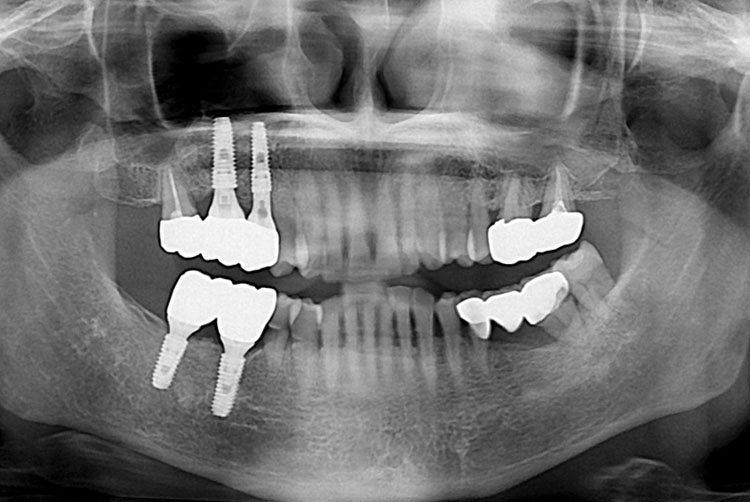

[임플란트] 임플란트

치료후 : 2017-03-23

세종치과는 많은 환자와 다양한 케이스를 바탕으로 항상 편안한 임플란트 수술을 제공하고자 노력하고,

오래동안 튼튼히 쓸 수 있는 임플란트 수술을 가장 큰 목표로 삼고 있습니다.